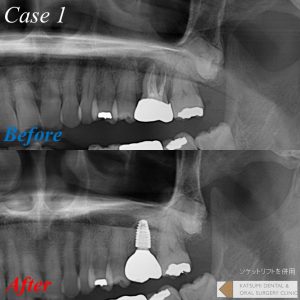

通常抜歯をしてしまうと歯槽骨が吸収し、特に上顎臼歯部では上顎洞という空洞が存在するため、将来的にインプラントを行うための骨の高さが不足し、埋入が不可能となったりおおがかりな骨移植が必要となってしまいます。そのような場合、抜歯と同時に骨を再生するための骨補填材を抜歯窩に填入することによって、骨吸収を抑制し、骨の回復と再生スピードを上げることが可能となります。当院では症例および患者さんの要望に合わせ、様々な骨補填材を選択しており、更に血液から作る再生療法も提供しています。

提示の症例では、更に「ソケットリフト」という骨を槌打して骨を挙上させかつ圧縮して骨密度を高める術式を併用することによって、よりインプラントがしっかり安定できるようにしております。